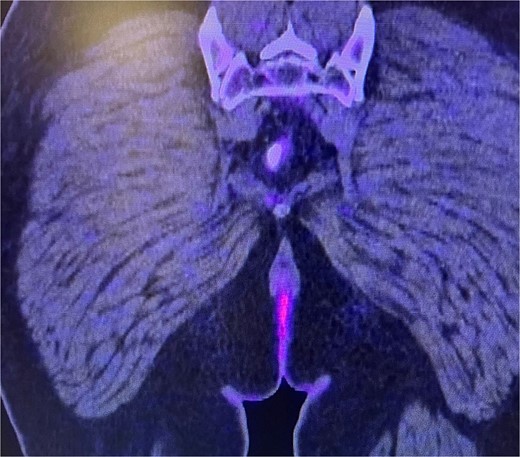

Consequently, an abdominal and pelvic magnetic resonance imaging (MRI) was performed (Fig. 4), which revealed a 16 x 22 mm mass in the perianal region, characterized by asymmetric thickening affecting both the external and internal sphincters, just at the anodermic junction, with extension into the elevator ani muscles.

Abdominal and pelvic magnetic resonance imaging. The white arrow points to a 16 x 22 mm mass in the perianal region, where asymmetric thickening affecting both the external and internal sphincters is evident, located just at the anodermic junction and extending into the levator ani muscles.